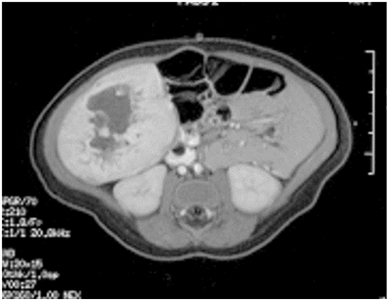

En las IRM, los tumores vasculares hepáticos son hiperintensos en las imágenes T2 e hipotensos en las imágenes T1; las imágenes después del contraste exhiben realce periférico temprano con realce difuso posterior.[

Las lesiones se suelen dividir en las siguientes 3 categorías:[

En una clasificación más adecuada se usa una evaluación interdisciplinar, que incluye la clasificación patológica con evaluación genómica, la evaluación radiológica por imagen, así como los antecedentes y exámenes clínicos; esto se fundamenta en las clasificaciones de la ISSVA y la OMS. En un estudio se analizaron 33 casos de tumores vasculares hepáticos pediátricos a partir de sus características anatomoclínicas desde 1970 hasta 2021.[